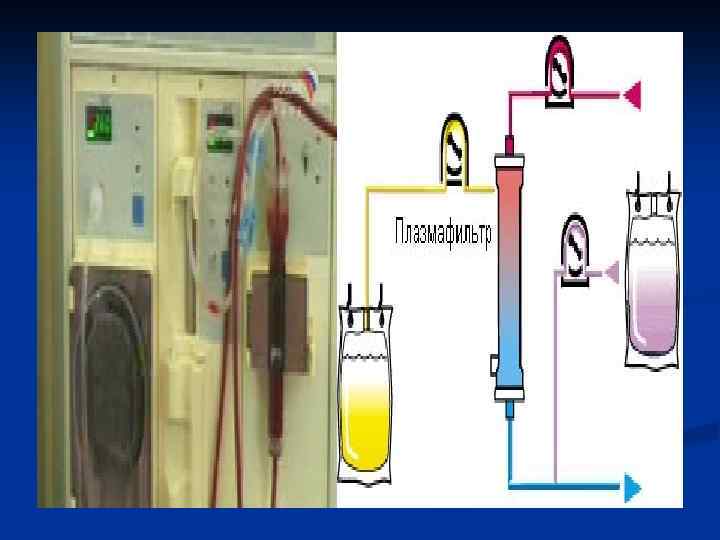

n Гемосорбцияны қандағы әр түрлі зиянды заттардан тазарту үшін қолданады. Ағзада әдетте бұл бауырдың жұмысы. «Гемо» -қан, «сорбция» -ағзаны уландырушы зиянды заттардан тазарту, яғни қанды, қан сары суын, лимфаны токсиндерден, улы заттардан тазарту үшін сорбентпен толтырылған арнаулы түтік арқылы сүзгіден өткізілуі.